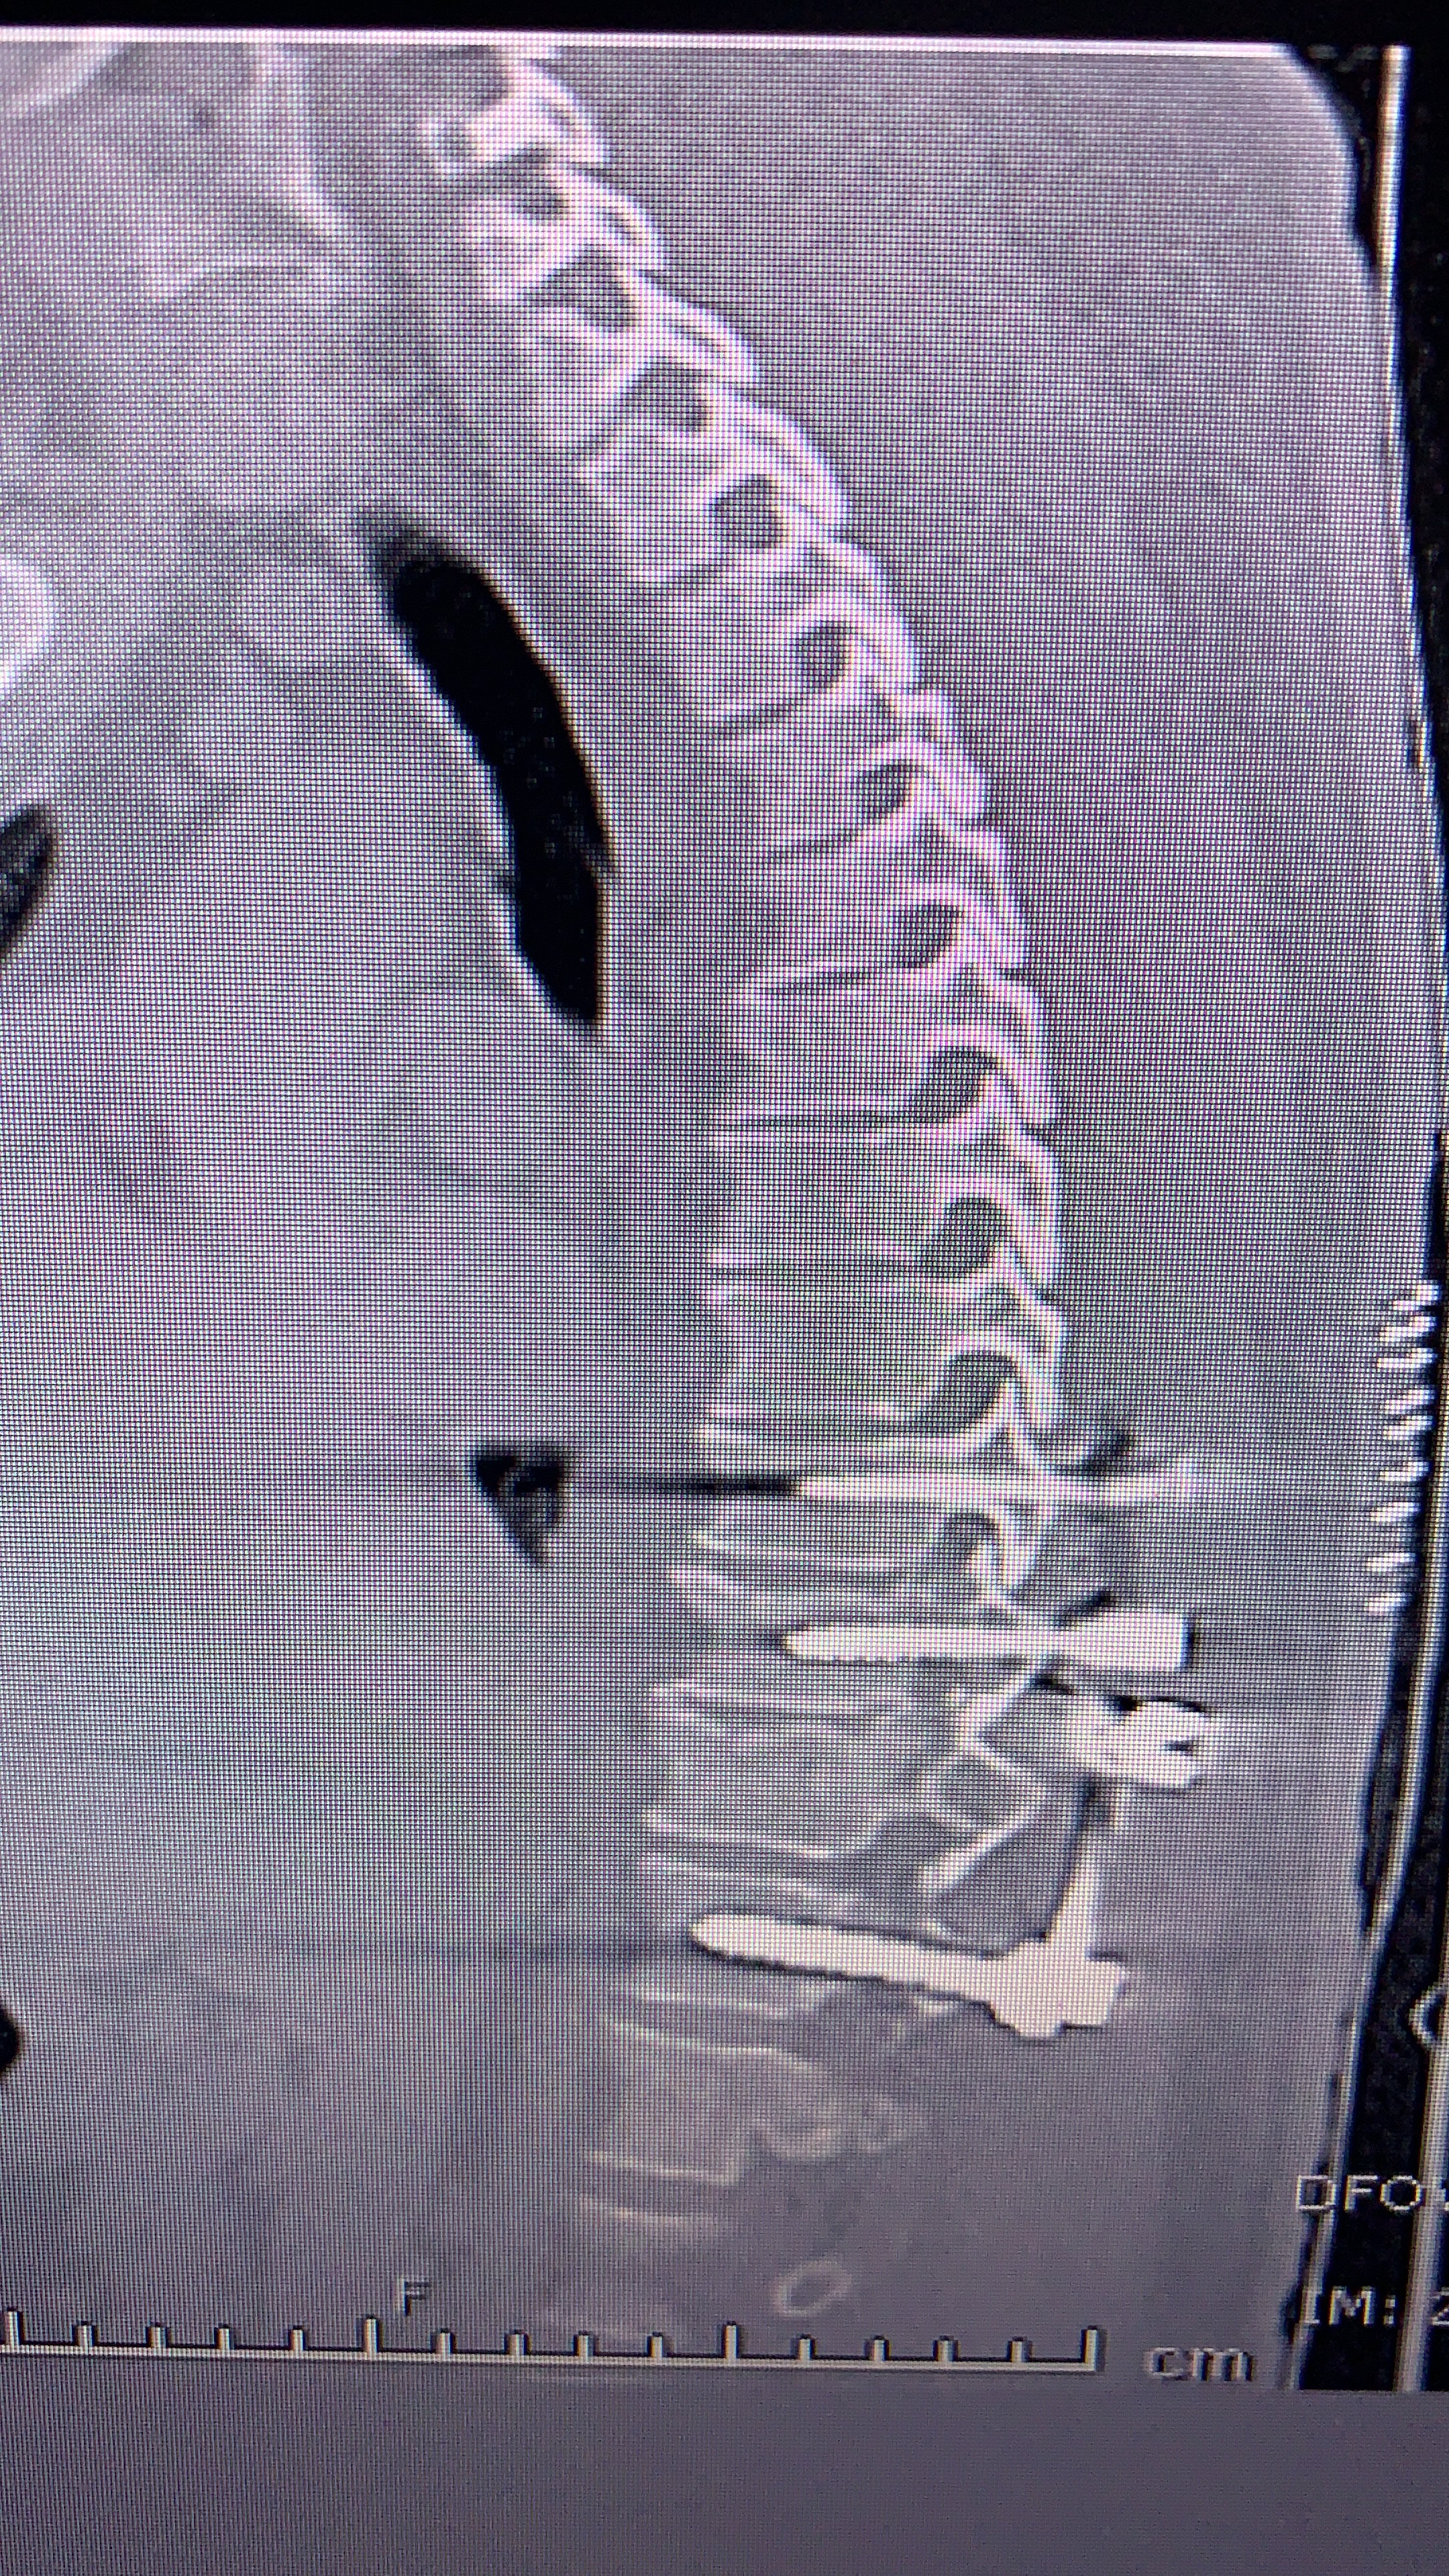

Galería de fotos clínica, servicios, cirugías, casos de pacientes Visítenos, ambiente limpio, agradable y seguro. Trabajando Operando en tiempos de coronavirus Dr Barquero Traumatologo Compartir en X (Se abre en una ventana nueva) X Comparte en Facebook (Se abre en una ventana nueva) Facebook Imprimir (Se abre en una ventana nueva) Imprimir Compartir en WhatsApp (Se abre en una ventana nueva) WhatsApp Enviar un enlace a un amigo por correo electrónico (Se abre en una ventana nueva) Correo electrónico Me gusta Cargando...